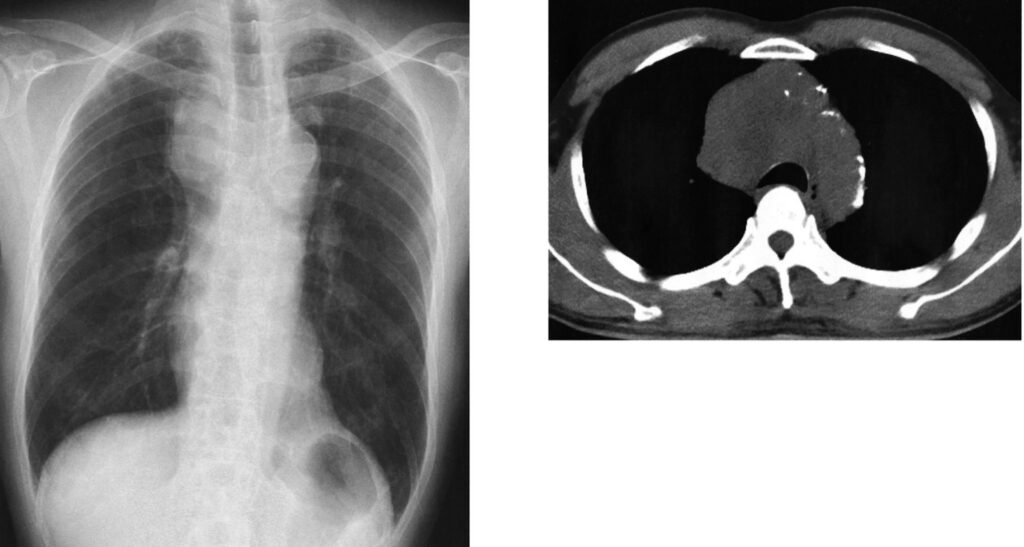

67歳の男性。労作時の息切れを主訴に来院した。1週間前から労作時の息切れ、右頸部から顔面の腫脹が出現したため自宅近くの診療所を受診した。胸部エックス線写真で右肺野に異常陰影を指摘されたため紹介受診した。胸痛や腹痛はない。意識は清明。身長 168 cm、体重 69 kg。体温 36.5 ℃。脈拍 84/分、整。血圧 138/78 mmHg。呼吸数 18/分。SpO2 96 %(room air)。頸静脈の怒張を認める。両側鎖骨上窩に径1~2cmのリンパ節を複数触知する。心音と呼吸音とに異常を認めない。腹部は平坦、軟で、肝・脾を触知しない。血液所見に異常を認めない。血液生化学所見で、腎機能と肝機能に異常を認めない。ProGRP 124 pg/mL(基準 81 以下)。胸部エックス線写真(別冊No. 14A)と胸部単純 CT(別冊No. 14B)とを別に示す。FDG-PETを施行し、右縦隔・肺門リンパ節と一塊となった腫瘤、多発肺転移および多発肝転移を認めた。気管支鏡検査を施行し腫瘤からの穿刺細胞診で小細胞肺癌と診断された。